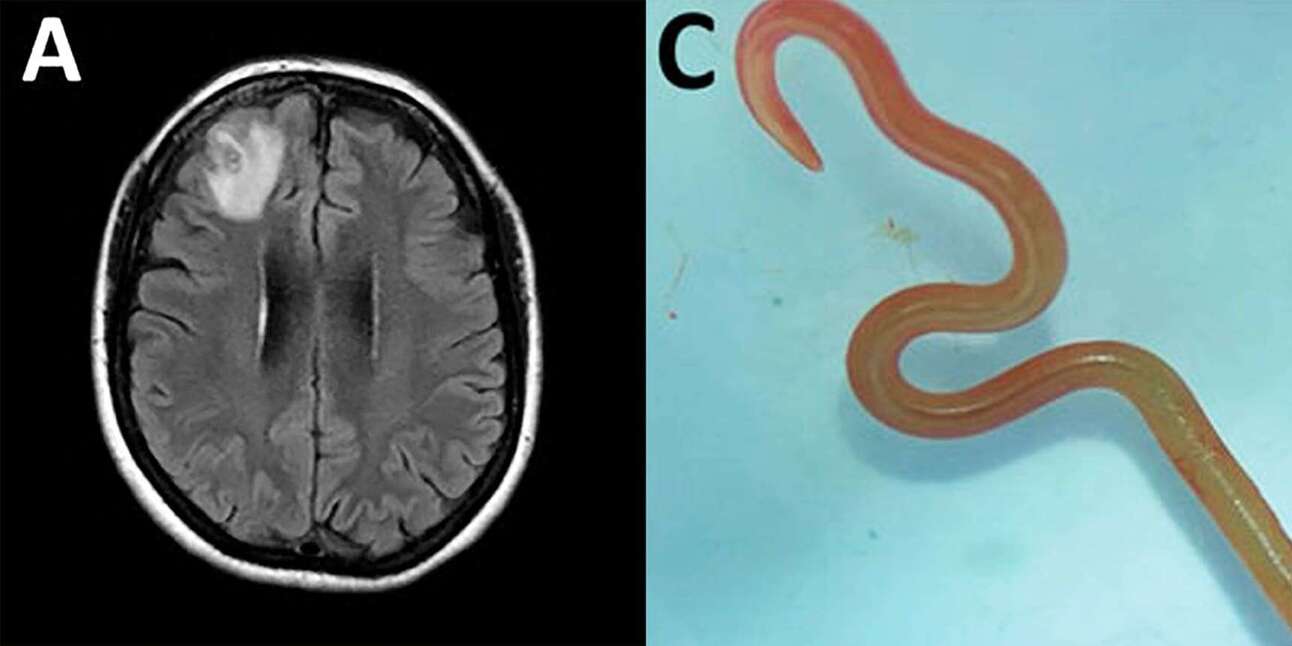

Jeżeli czytacie .dzień dobry do śniadania — polecamy na sekundkę odstawić jajka po benedyktyńsku. Australijska neurochirurg po raz pierwszy w historii usunęła robaka, który squatował w mózgu człowieka.

WTF: 64-letnia pacjentka, u której znaleziono niepożądanego gościa, przez dwa lata dosłownie żyła w odcinku dr House’a.

W 2021 roku po raz pierwszy zgłosiła się do szpitala z symptomami bólu brzucha, suchego kaszlu i nocnych potów.

Z czasem doszły problemy z pamięcią i depresją.

Finalnie wylądowała na oddziale neurologicznym, z podejrzeniem raka mózgu.

Po tym jak rezonans magnetyczny wykazał niezidentyfikowane zmiany w prawym płacie czołowym lekarze postanowili wykonać biopsję mózgu w celu ukończenia diagnozy.

W trakcie zabiegu dr. Hari Priya Bandi przeżyła największy zonk jaki neurochirurg może przeżyć w trakcie kariery — w pewnym momencie złapała szczypcami obiekt, który okazał się być żywym, ruszającym się robakiem, o długości 8 centymetrów.

Co w tym ważnego: odkrycie dr. Bandi jest nieapetyczne, lecz bardzo znaczące dla naukowców.

Do tej pory nie udokumentowano ataków pasożytów na mózg nie tylko człowieka, ale jakiegokolwiek ssaka.

Obecność robaków z tego gatunku potwierdzona była tylko w przypadku węży, a w szczególności pytonów.

Tak właśnie tłumaczona jest obecność pasożyta w mózgu pacjentki, która mieszka w pobliżu jeziora zamieszkiwanego przez pytony dywanowe. Naukowcy spekulują, że gady pozostawiły część insektów na owocach leśnych, które kobieta następnie zebrała i dodała do posiłku.

Co dalej: odkrycie jest przykładem kolejnej choroby zakaźnej, która przechodzi ze świata zwierząt na ludzi (poprzednim przykładem był covid).

Naukowcy zwracają uwagę, że w ostatnich latach liczba chorób przenoszących się ze zwierząt na ludzi narasta i wynika z dysproporcji naszej populacji w porównaniu z resztą ekosystemu.

Zupełnie przy okazji — do arachnofobów dołączyła właśnie spora grupka osób, które nigdy, przenigdy w życiu nie pojadą do Australii.